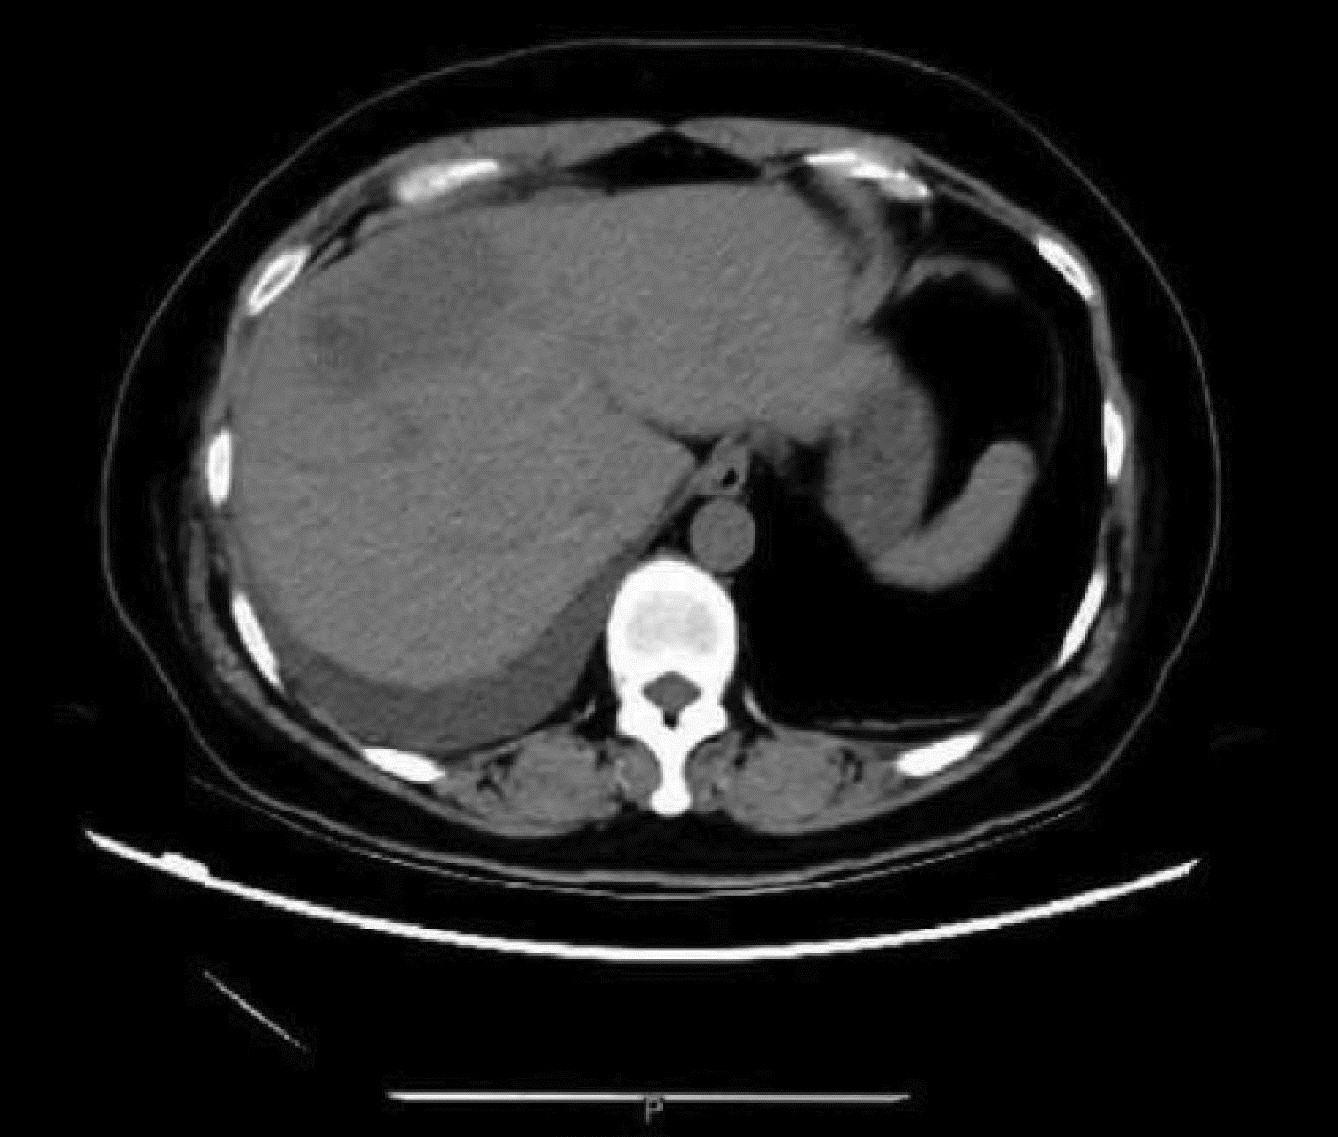

巨大肝血管瘤伴弥漫性动脉-门静脉瘘1例报告

周帮健, 杨俊, 印于, 朱晓黎, 倪才方, 王万胜

2023, 39(3): 640-643. DOI: 10.3969/j.issn.1001-5256.2023.03.025

摘要(1061) HTML (229) PDF (3500KB)(116)

摘要: